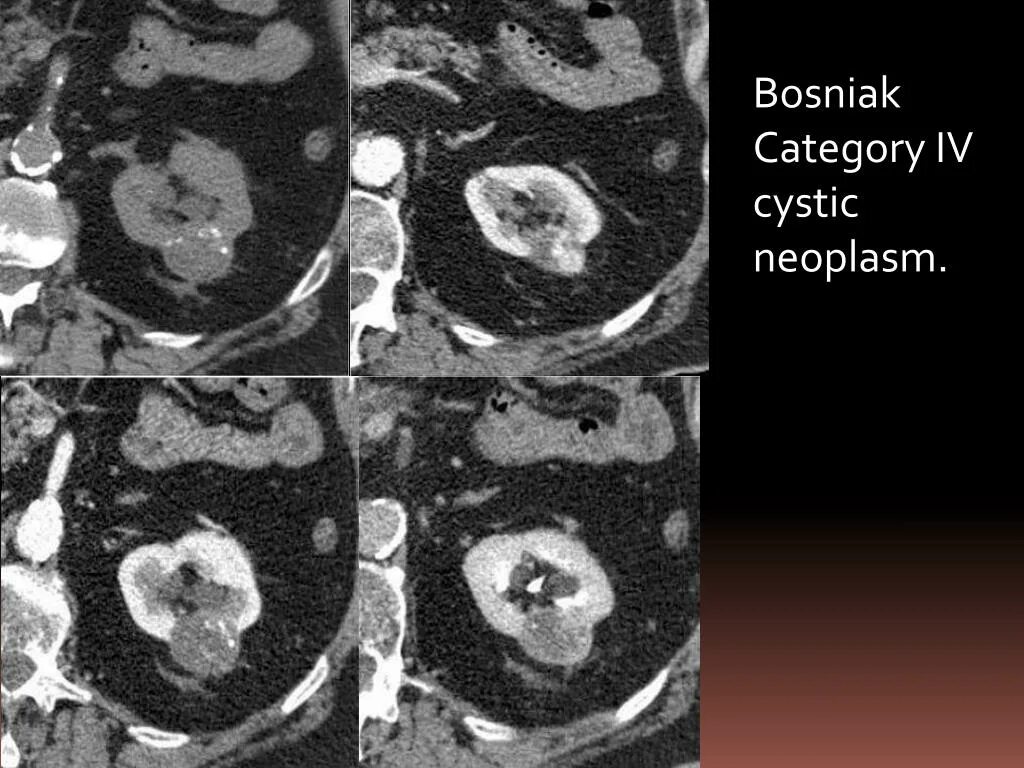

Кисты почек bosniak